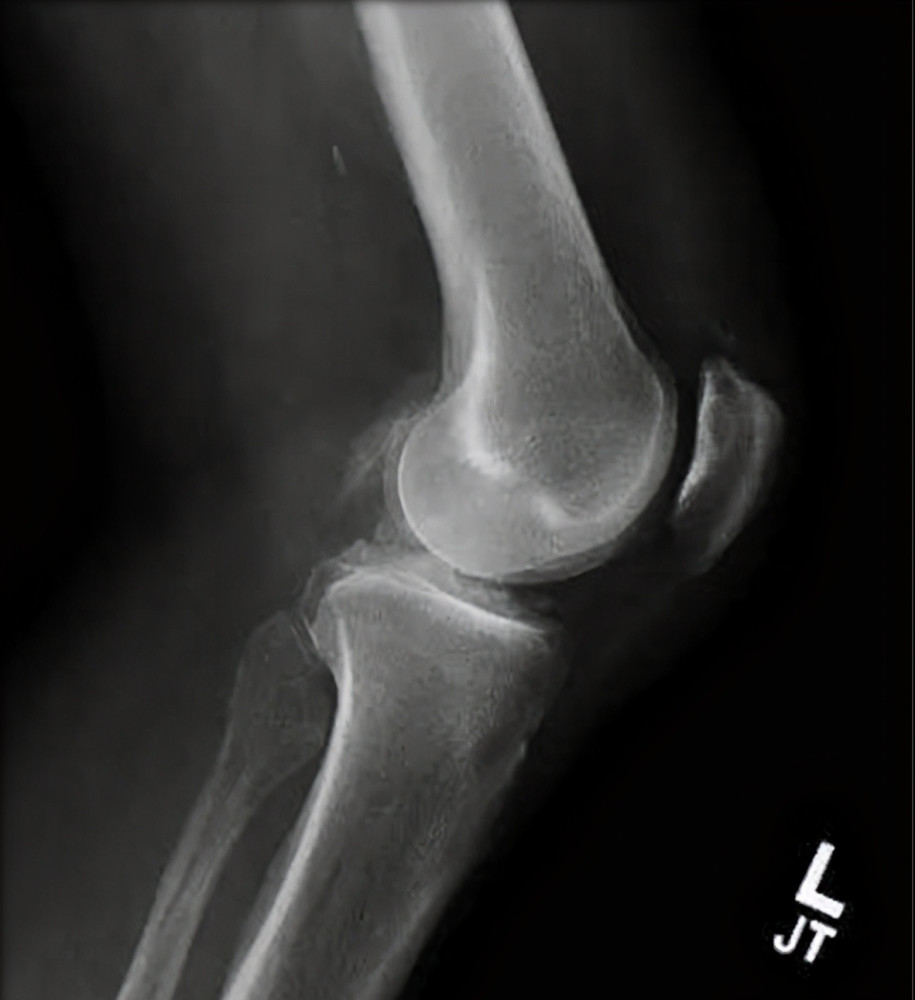

X光片也有助于诊断 , 因为焦磷酸钙晶体会阻断X光射线而在X光片上显出白色沉淀物轮廓 , 而尿酸盐晶体则没有这样的特征 。 即使在假性痛风没有临床急性发作时 , X光片仍可能在受累关节和典型关节中可见关节软骨呈点状和线状钙化斑 , 软骨钙化有助于确诊(特别是膝关节、腕关节等大关节) , 并可以了解到关节退化的范围 。 此时做关节腔穿刺 , 也可见关节液具有炎性特征 。